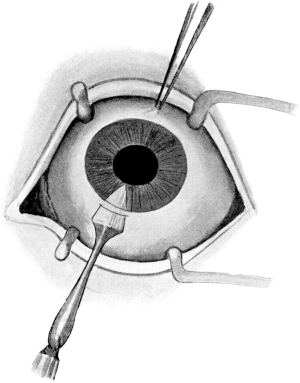

| 94. | Lens Extraction | 196 |

| 95. | The Knife entering the Anterior Chamber in Cataract Extraction | 197 |

| 96. | Making the Counter-puncture in Cataract Extraction | 197 |

| 97. | Incision and Iridectomy in Cataract Extraction | 198 |

| 98. | Opening the Capsule with Forceps in Cataract Extraction | 199 |

| 99. | Cataract Extraction | 200 |